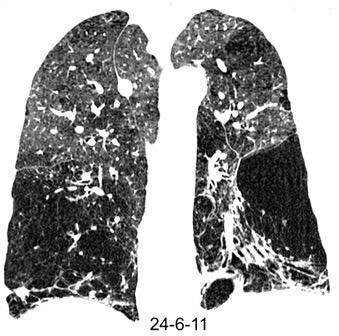

LESIÓN “QUÍSTICA MÚLTIPLE.

Linfangioleiomiomatosis

Mujeres en edad gestante

Quistes de pared fina No distribución zonal Bilaterales

Patrón reticular (si muchos)

Neumotórax frecuente Hallazgos similares a la Esclerosis tuberosa.

Histiocitosis de Langerhans

Jóvenes fumadores.

(entre 20-40 años)

La mayoría sin síntomas.

Neumotórax: 5%.

Complicación: Diabetes insípida.

1º Nódulos

2º. Quistes. Progresan a formas extrañas.

Suelen dejar libres las bases pulmonares

Raoof L et al. Cystic Lung Diseases, Chest 2016